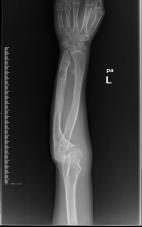

桡骨陈旧性骨折骨不连、畸形

先天性胫骨假关节

肢体短缩延长术,延长9厘米

术前 手术 术后功能恢复良好

肱骨外髁陈旧性骨折

弹性髓内钉治疗股骨骨折

尺骨短缩畸形并软骨瘤 桡骨小头脱位